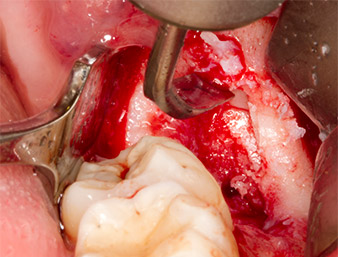

Tras una anestesia local y por conducción, el campo quirúrgico se abrió mediante los tejidos blandos para tener un acceso bucal-retromolar y se dejó expuesto (figura 3).

El tejido situado por encima del resto radicular no se había osificado por completo y constaba en su mayor parte de un tejido granulado con alteraciones inflamatorias (figura 4).